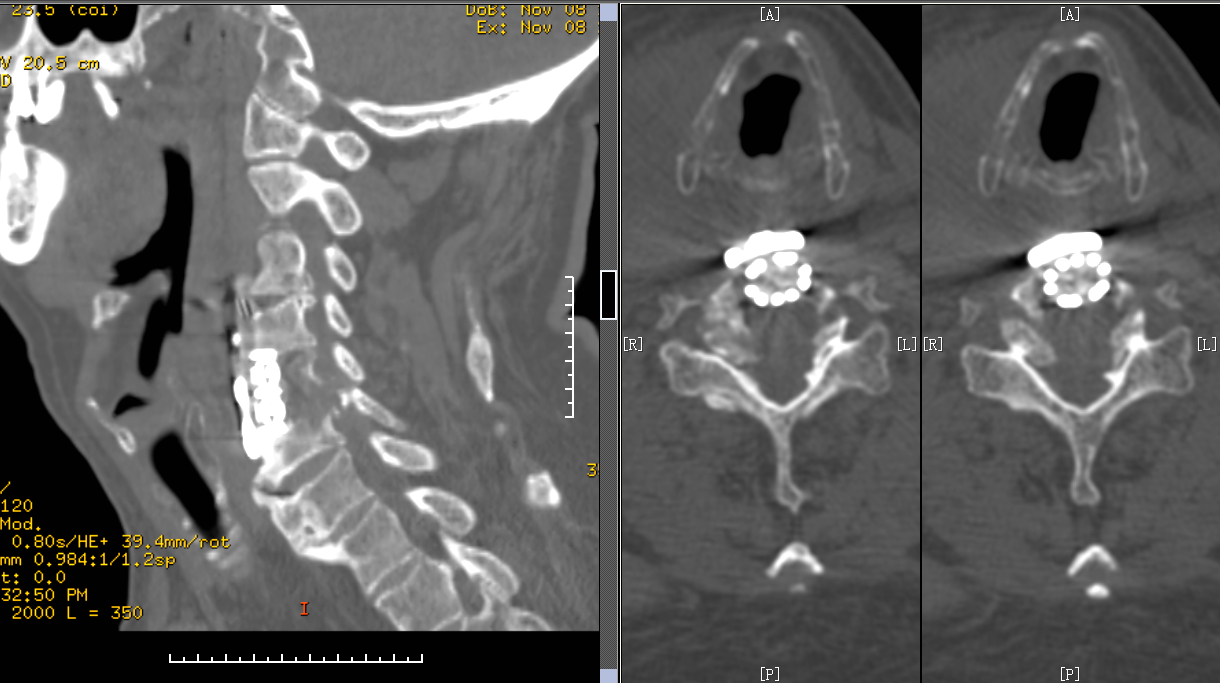

颈椎CT

诊断:颈椎后纵韧带骨化、颈椎过伸伤、颈椎间盘突出

手术术式:显微镜辅助下ACCF

术后CT矢状位

术后CT横断面